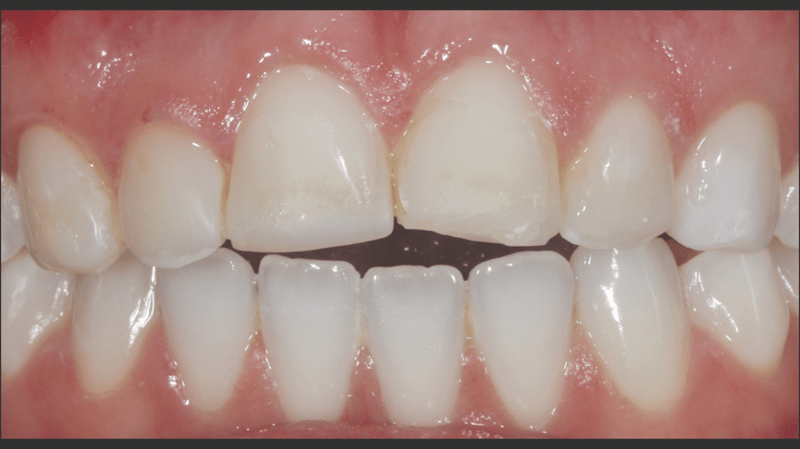

Eine junge Frau in den 20ern stellte sich in der Praxis von Dr. Jaleena Fischer-Jessop, DDS, MBA, vor. Sie hatte Verfärbungen im oberen Frontzahnbereich, welche durch ein Trauma verursacht worden waren und wünschte sich eine Lösung für ein ästhetischeres Lächeln. Die Behandlung der Patientin erfolgte mit einer konservativen und kostengünstigen Lösung: direkte Non-Prep-Veneers. Dr. Fischer-Jessop entschied sich für diese Vorgehensweise, um die Verfärbung abzudecken, die oberen Frontzähne der Patientin an die unteren anzugleichen und invasivere Methoden wie Implantate oder teure, im Labor hergestellte Veneers zu umgehen. Die Farben B1D und Enamel White (EW) wurden zur Aufhellung der Zähne verwendet. Das Transcend™ Komposit (Farbe „Universal Body“, UB) sorgte für einen natürlichen Übergang zwischen den Randbereichen und den zervikalen Bereichen.

- Ästhetische und finanzielle Aspekte: Die Patientin war unzufrieden mit dem Erscheinungsbild ihrer Zähne und zudem finanziell eingeschränkt. Vor diesem Hintergrund fiel die Entscheidung auf eine Behandlung mit direkten Non-Prep-Veneers.

Mit dem durchgeführten Behandlungsprotokoll konnten die ästhetischen Anforderungen der Patientin erfüllt werden. Die Verfärbung der oberen Frontzähne wurde kaschiert und ein natürliches, auf die unteren Frontzähne abgestimmtes, Erscheinungsbild wurde erzielt. Die Verwendung von direkten Non-Prep-Kompositveneers war dabei eine konservative, höchst effektive Lösung, die sowohl den finanziellen Möglichkeiten der Patientin als auch ihrem Wunsch nach minimal-invasiven Methoden Rechnung trug.